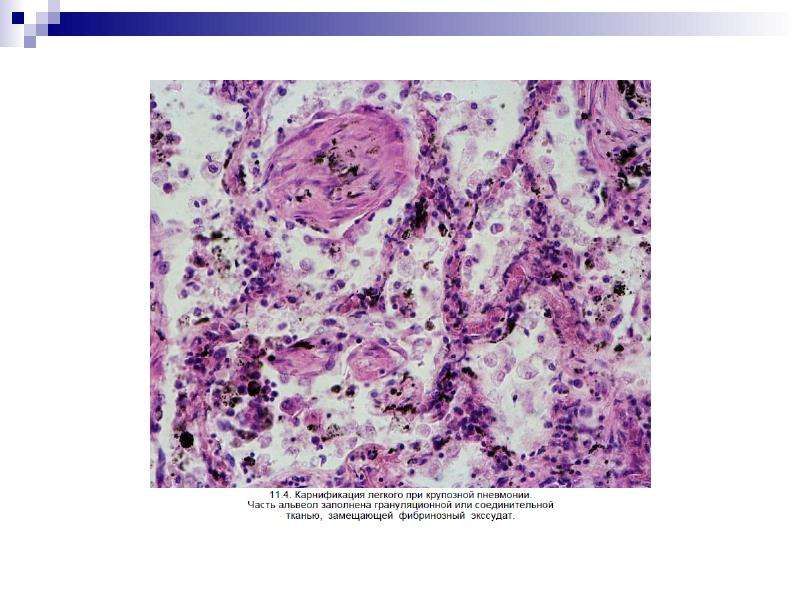

Карнификация Легкого: Микропрепараты и Диагностика

Раздел: Калейдоскоп образов